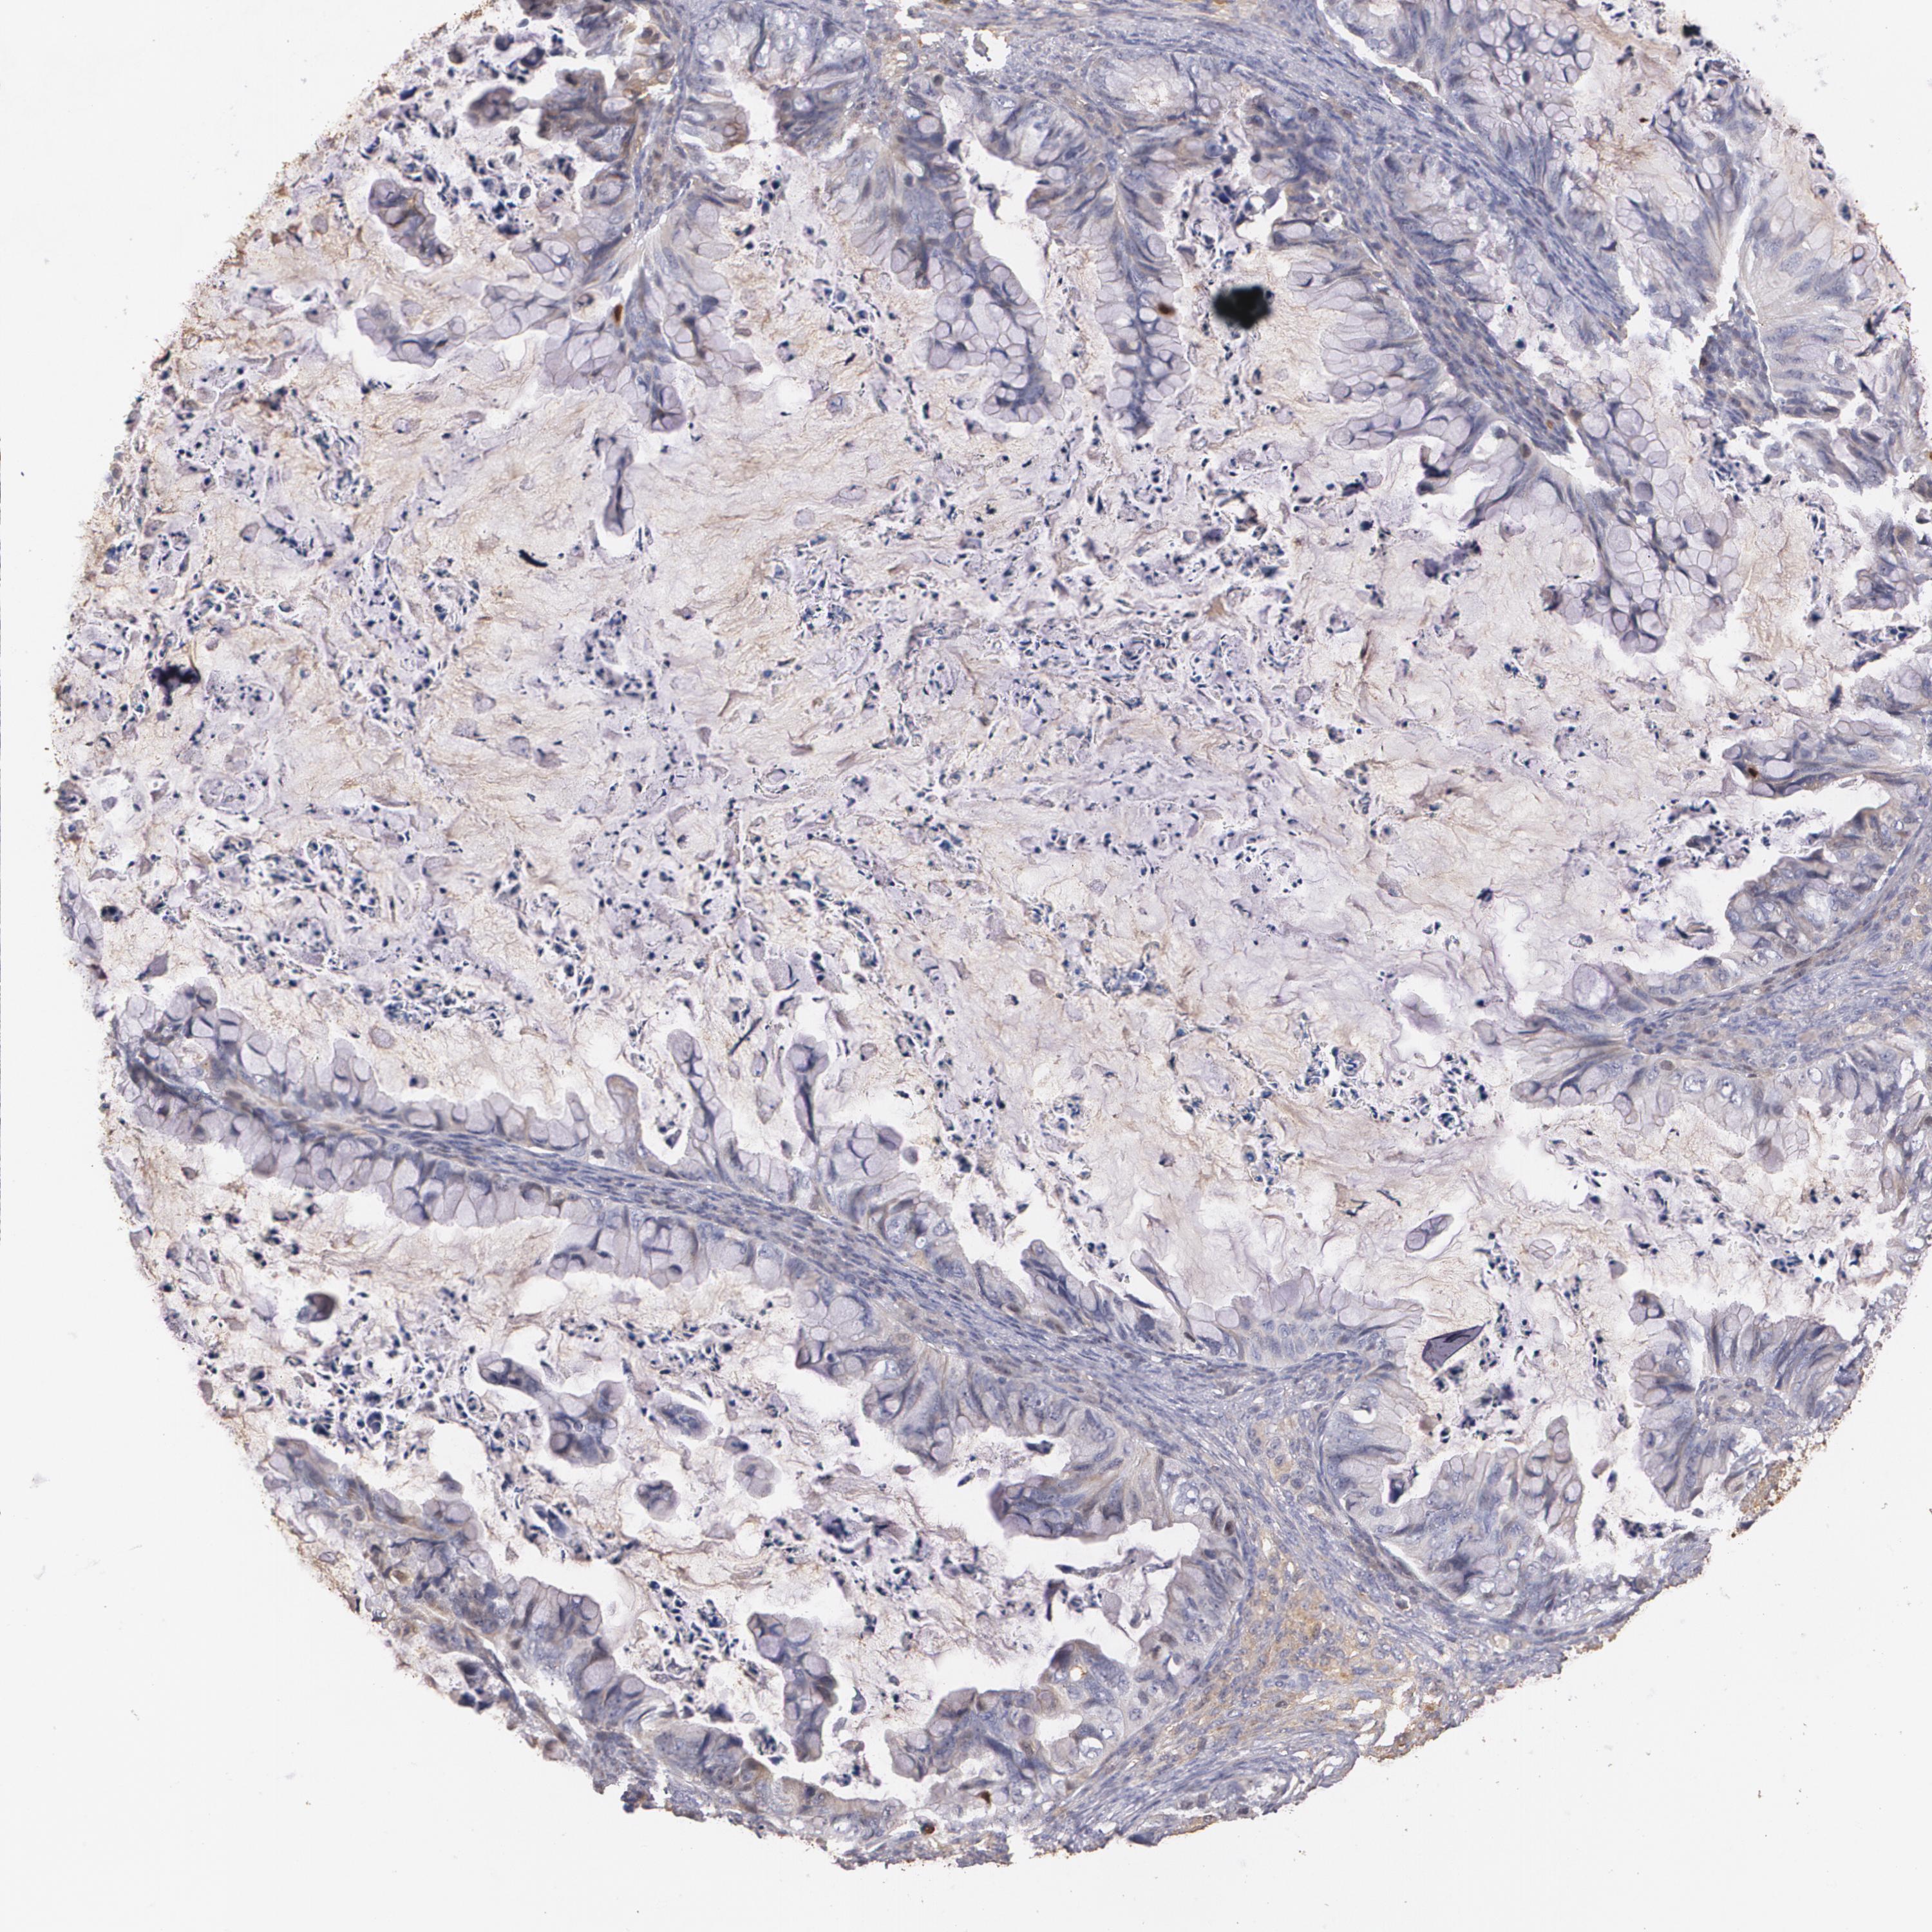

OVARIAN CANCER - Protein expressioni

A mouse-over function shows sample information and annotation data. Click on an image to view it in a full screen mode. Samples can be filtered based on level of antibody staining by selecting one or several of the following categories: high, medium, low and not detected. The assay and annotation is described here.

Note that samples used for immunohistochemistry by the Human Protein Atlas do not correspond to samples in the TCGA dataset.

Antibody stainingi

Antibody staining in the annotated cell types in the current human tissue is reported as not detected, low, medium, or high, based on conventional immunohistochemistry profiling in selected tissues. This score is based on the combination of the staining intensity and fraction of stained cells.

Each image is clickable and will lead to virtual microscopy that enables deeper exploration of all samples and also displays staining intensity scores, fraction scores and subcellular localization as well as patient and tissue information for each sample.

Antibody HPA001481

Staining

High

Medium

Low

Not detected

Intensity

Strong

Moderate

Weak

Negative

Quantity

>75%

75%-25%

<25%

None

Location

Nuclear

Cytoplasmic/membranous

Cytoplasmic/membranous,nuclear

Cystadenocarcinoma, serous, NOS

Cystadenocarcinoma, mucinous, NOS

Carcinoma, endometroid